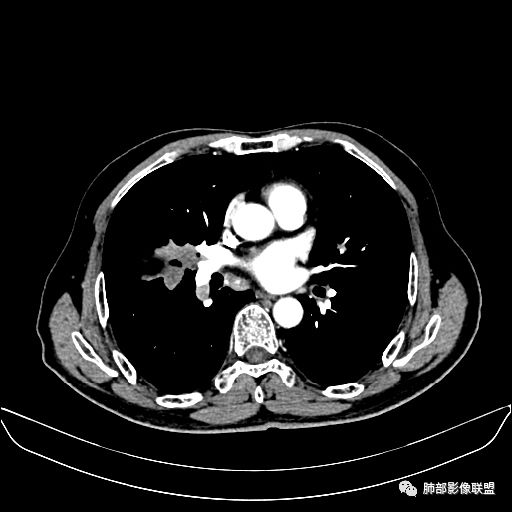

住院4天后行胸部增强CT

静脉期

老年男性,因“咳嗽咳痰1月余。”入院。病程中咳嗽咳痰,咳黄白痰,间断咯少许鲜红色痰血。PPD阳性。胸CT:右肺中叶外侧段支气管管腔阻塞,大片实性病变,病灶边缘光滑,部分边缘膨隆,可见分叶,肺门及纵隔可见肿大淋巴结,并可见钙化。增强可见病灶明显强化,而且延迟强化明显,病灶内多发低密度区,内见血管影,血管变细、部分血管破坏。考虑恶性病变可能性大,鉴别慢性肉芽肿性病变。

胸CT:跨叶大肿块,主体在中叶,右中叶外侧段支气管阻塞,病灶部分边缘膨隆,可见分叶,部分边缘平直,肺门及纵隔可见肿大淋巴结。增强病灶不均匀强化,延迟强化明显,病灶内多发低密度区,内见血管飘浮,部分血管变细、模糊。考虑:恶性病变可能性大,大细胞?淋巴瘤?鉴别慢性肉芽肿性病变。

吴婧老师和南边老师都对该病例进行了深入分析。从支气管管壁的增厚,支气管狭窄后扩张,支气管粘液栓,病灶形态,到病灶不均匀强化及坏死彻底,到周边病灶及肺组织空气的潴留,加之纵隔内淋巴结肿大伴钙化等等,都支持慢性炎性病灶,尤其是结核。

墨西哥仙人掌征---结核        影像上结核灶,粗大的均匀枝干,推测是支气管囊状扩张引起的,在非支气管区,形成圆形坏死囊群;如果这些坏死比较稀薄,又遇到扩张支气管,就会形成粗大的“墨西哥仙人掌”。结核引起的支气管近端炎症纤维化,可以造成支气管阻塞,从而将干酪样坏死物封堵在管腔内。仙人掌主干内部应该是干酪为主,稀薄的,具有流动性,时间久了会出现钙化。